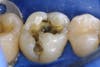

Mercury (as in a thermometer) expands and contracts with change in temperature, every time you consume anything hot or cold. This amalgam filling is sitting in a tooth that resembles glass or china. This chunk of metal then expands and contracts within this brittle tooth. So what do you think it will do to the tooth surrounding this material? That’s right, it will cause fractures. Fractures can break the tooth. How many of you have had a crown because your tooth broke but the filling was still intact?! Fractures also will leak, allowing bacteria to penetrate within, causing decay (cavities). The photos I have posted to this blog clearly show what we see when we remove the amalgam.